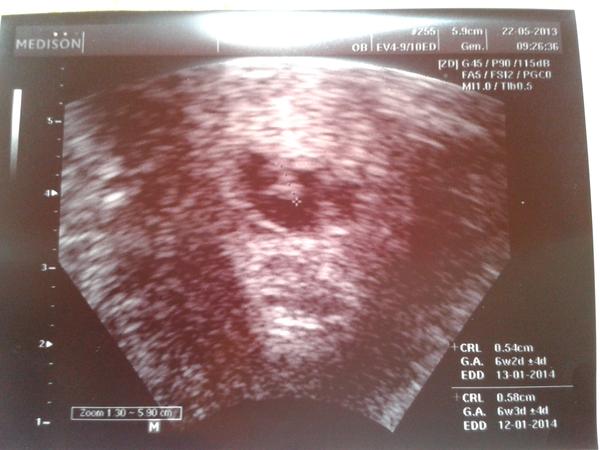

Ahoj holky...hcg nestoupla podle představ doktora ,ale udělal utz pro vyloučení mimoděložního....jaké překvapení tam na nás vykouklo....zavolal i přítele ať se jde podívat na zázrak...holky a ono mělo i náznak srdíčka!!!!minule ani bublinka protě prázdno a teď toto. Mám tam sice ještě malý hematom, ale je menší než plod takže to je prý dobré. Tak teď už je to na bojovníčkovi jak to zvládne....